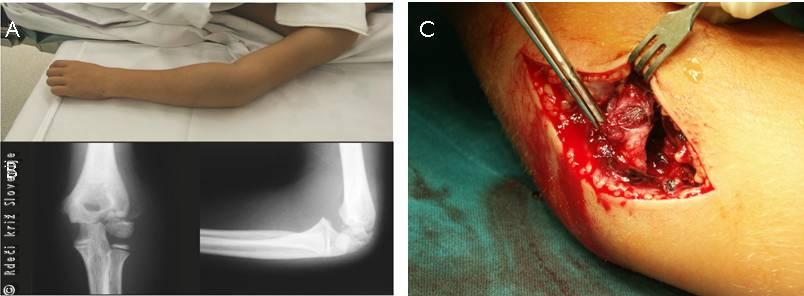

Primer 2

8-letni deček je med igro padel in se udaril v levi komolec. Prepeljali so ga v urgentno ambulanto, kjer je bila ob pregledu prisotna oteklina v predelu levega komolca. Boleč je bil pritisk na glavico koželjnice ter srednji del podlakti. Gibanje v komolcu ni bilo mogoče. Ni bilo znakov za poškodbo žil ali živcev. Rentgenska slika je pokazala zlom spodnjega dela podlahtnice. Potrebna je bila odprta naravnava in učvrstitev zloma.

Slika 13

Zlom v predelu komolca.

A – Vidna je oteklina v zgornjem delu podlakti.

B – Rentgenska slika pokaže zlom zgornjega dela podlahtnice.

C – Zlom je potrebno naravnati z operacijo.